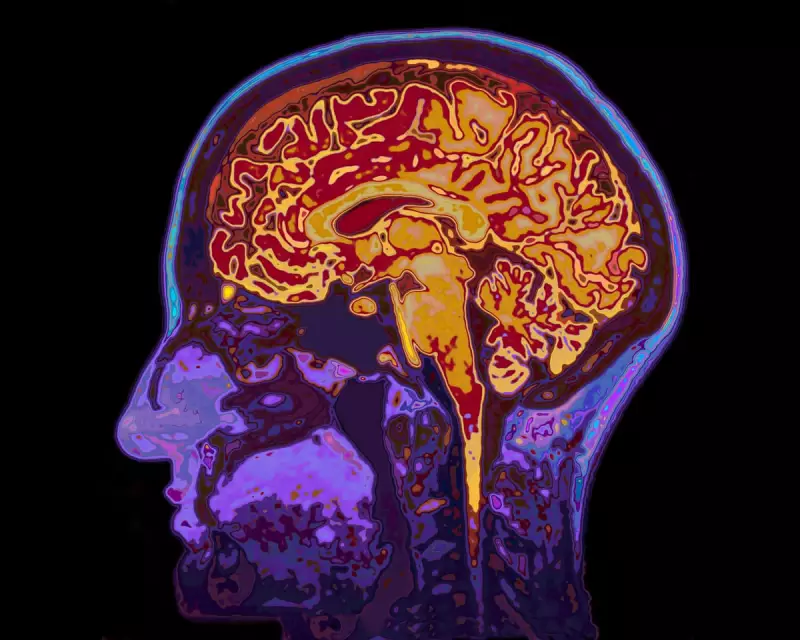

Scientists have discovered that sleep deprivation doesn't just make you feel groggy - it fundamentally disrupts how different regions of your brain communicate. Using advanced brain scanning technology, researchers observed how tired brains struggle to maintain coordinated activity between key networks responsible for attention and focus.

The study reveals that when we're exhausted, our brain's executive control network - the system that helps us concentrate - becomes less effective at suppressing the default mode network, which is typically active when our minds wander.